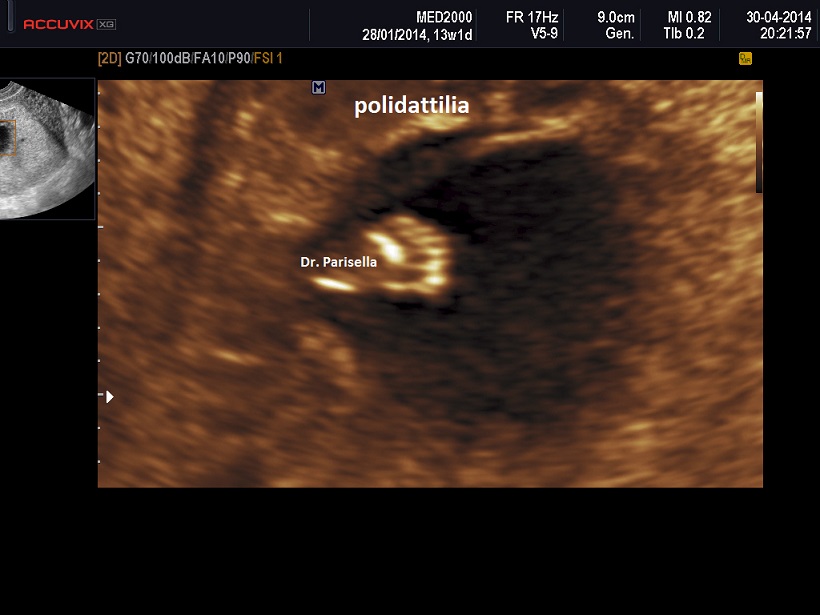

E' una malattia trasmessa con carattere autosomico recessivo caratterizzata da Polidattilia per lo più postassiale, Reni Policistici, Encefalocele Occipitale, Oligoamnios/Anidramnios in fase avanzata di gravidanza, Displasia Duttale Epatica.

La diagnosi ecografica prenatale si basa sulla triade: ENCEFALOCELE OCCIPITALE, POLIDATTILIA, RENI POLICISTICI.

I tre tipi, a diversa espressione genetica, hanno diversa espressione fenotipica. La polidattilia frequente in MKS1 è rara in MKS3. La MKS1 ha anche una variante campomelica.